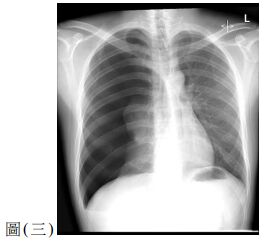

10. 一位60歲女性因腹痛、噁心與嘔吐來急診。此病人有剖腹產與膽囊切除手術病史,其KUB如圖(二),請問最有可能的診斷為何?

(A) 沾黏性小腸阻塞( adhesive small bowel obstruction )(B) 大腸阻塞(large bowel obstruction )(C) 缺血性大腸炎(ischemic colitis)(D) 小腸憩室炎(small bowel diverticulitis)